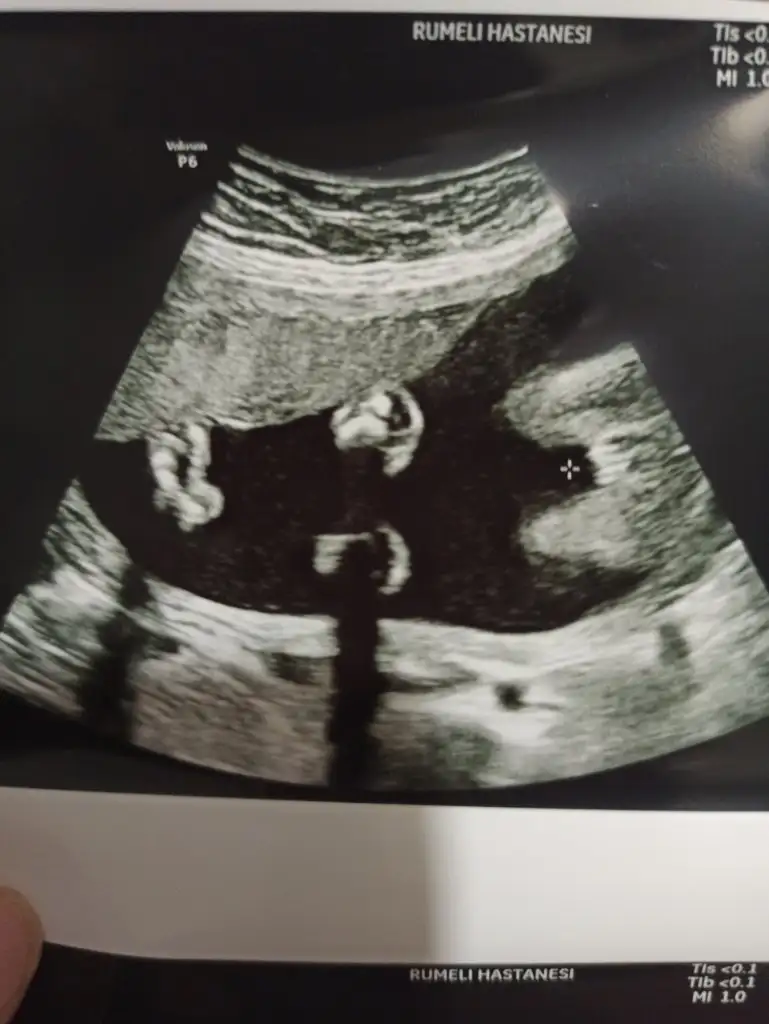

Sağlıkla gelsinBugün ki ultrason fotoğrafı